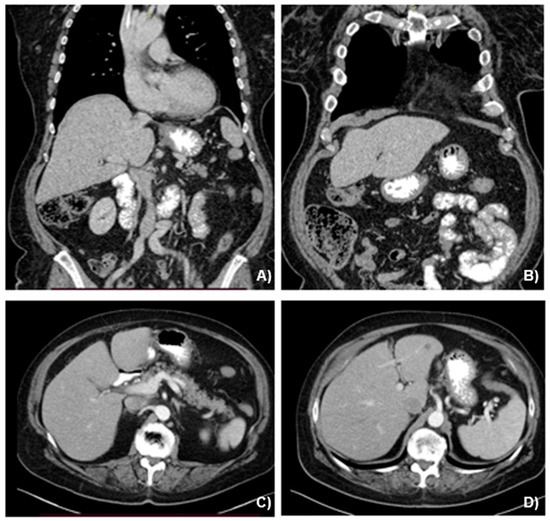

A 69-year-old female, with an unremarkable medical history, underwent an upper-GI endoscopy for progressive dysphagia for solid and liquids. A brittle ulcerous lesion with partial occlusion and signs of recent hemorrhage was detected at the EGJ with expansion to the lesser curvature of the gastric cardia, classified as a Siewert III tumor (Figure 1). The histopathological analysis of the endoscopic biopsies revealed a poorly differentiated invasive adenocarcinoma with HER-2 expression to be negative. The clinical staging included computed tomography (CT) (Figure 2) followed by a staging laparoscopy. Imaging demonstrated a locally advanced tumor (cT4) with a bulky locoregional lymph node packet (cN+) and three liver lesions consistent with hepatic metastases. In front of a possible oligometastatic state of disease, a staging laparoscopy took place to exclude peritoneal seeding and facilitate the application of a percutaneous feeding tube. During laparoscopy, macroscopic peritoneal seeding was excluded, while both the bulky lymph nodes at the lesser curvature and the largest liver metastasis at the left liver lobe could be visually detected (Figure 3). Remarkably, these tumorous lesions demonstrated a soft consistency in palpation with the laparoscopic forceps, which was not expected, as metastatic lesions from adenocarcinoma primary are anticipated to have a solid and hard texture. Therefore, a lymph node biopsy at the lesser curvature of the stomach was contacted in order to exclude different histopathology. The peritoneal cytology after collection of peritoneal washings proved to be negative.

Figure 2. (A,B) Initial abdominal computed tomography in coronal and (C,D) axial views, depicting the gastric lesion and liver metastatic lesions (red arrows).